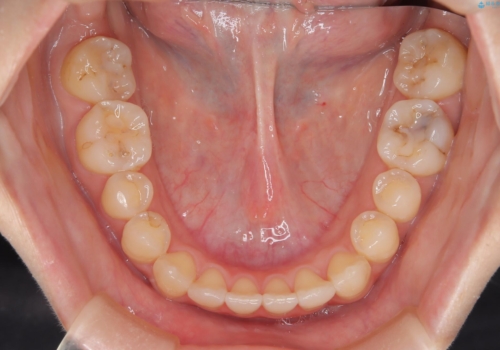

前歯のガタつき、下顎の前突感を治したい インビザライン矯正例

- 学生時代に矯正治療を経験されていましたが、その後の後戻りによる前歯の叢生・下顎の前突感を主訴に来院されました。叢生や口元の突出感が軽度であった為、非抜歯にて側方拡大やIPRを組み込んでインビザラインにて治療を計画しました。前歯部にクロスバイトがあり、治療途中に上顎前歯が下顎前歯を乗り越えなければならない時期もありましたが、患者様の協力的なマウスピース装着もあり、良好な配列を達成しました。上下左右の親知らずは、当院にて矯正開始前に抜歯しました。